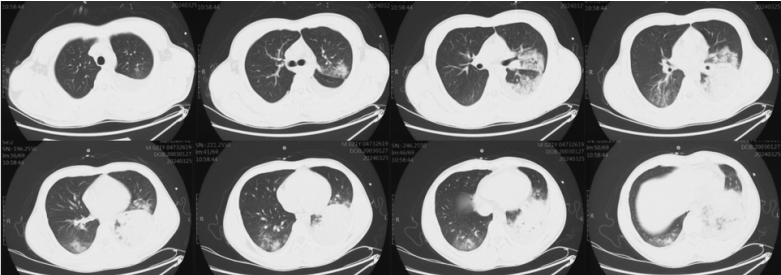

考虑到患者可能是病毒血症引起的全身非感染性炎症反应,于第7天决定选择甲泼尼龙(160 mg)给药1次,之后患者整体情况有所改善。密切监测其病原学,最终仅检出白色念珠菌,未在激素应用过程中出现曲霉感染。ECMO支持后(第8天)复查胸部CT可见双肺近乎完全实变,下肺尤为严重,肺内几乎没有有效通气(图4)

图片

图4  患者入院后胸部CT第8天